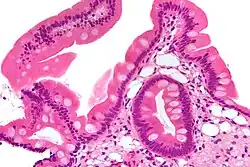

| Low magnification micrograph of Whipple's disease showing the characteristic foamy appearing infiltrate of the lamina propria. Duodenal biopsy. H&E stain. | |

Endoscopy of the duodenum and jejunum can reveal pale yellow shaggy mucosa with erythematous eroded patches in patients with classic intestinal Whipple's disease, and small bowel X-rays may show some thickened folds. Other pathological findings may include enlarged mesenteric lymph nodes, hypercellularity of lamina propria with "foamy macrophages", and a concurrent decreased number of lymphocytes and plasma cells, per high power field view of the biopsy.

Diagnosis is made by biopsy, usually by duodenal endoscopy, which reveals PAS-positive macrophages in the lamina propria containing non acid-fast, Gram-positive bacilli.[5][a] Immunohistochemical staining for antibodies against T. whipplei has been used to detect the organism in a variety of tissues, and a polymerase chain reaction-based assay is also available,[5] which can be confirmatory if performed on blood, vitreous fluid, synovial fluid, heart valves, or cerebrospinal fluid.[11] PCR of saliva, gastric or intestinal fluid, and stool specimens is highly sensitive, but not specific enough, indicating that healthy individuals can also harbor the causative bacterium without the manifestation of Whipple's disease, but that a negative PCR is most likely indicative of a healthy individual.[5]